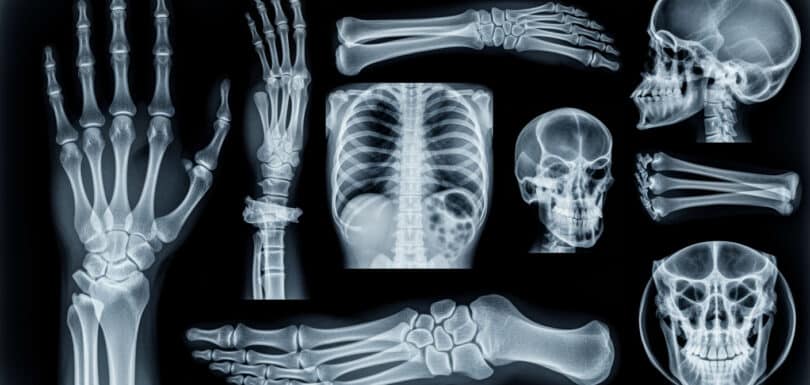

Urgent Care with Ultrasound Near Me in Odessa TX | Priority ER – 24/7 Urgent care with ultrasound near me is critical when experiencing abdominal pain, pregnancy complications, suspected blood clots, or vascular emergencies requiring immediate diagnosis. Priority ER provides 24/7 emergency ultrasound services with zero wait times, board-certified emergency physicians interpreting results immediately during […]